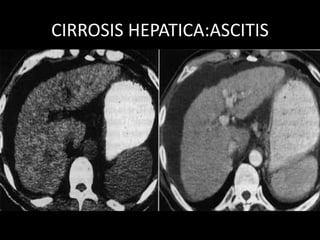

CIRROSIS HEPATICA

• Volumen hepático disminuido, bordes ondulados

• Parénquima con hiperecogenico, formado por ecos gruesos y

con atenuación posterior.

• VP incremento de diámetro, por encima de 14mm.

• VSH disminuidas de diámetro.

• VCI sin latido trasmitido

• Hipertrofia del segmento I, con hipoecogenisidad

• Ascitis

• Esplenomegalia

CIRROSIS HEPATICA:ASCITIS